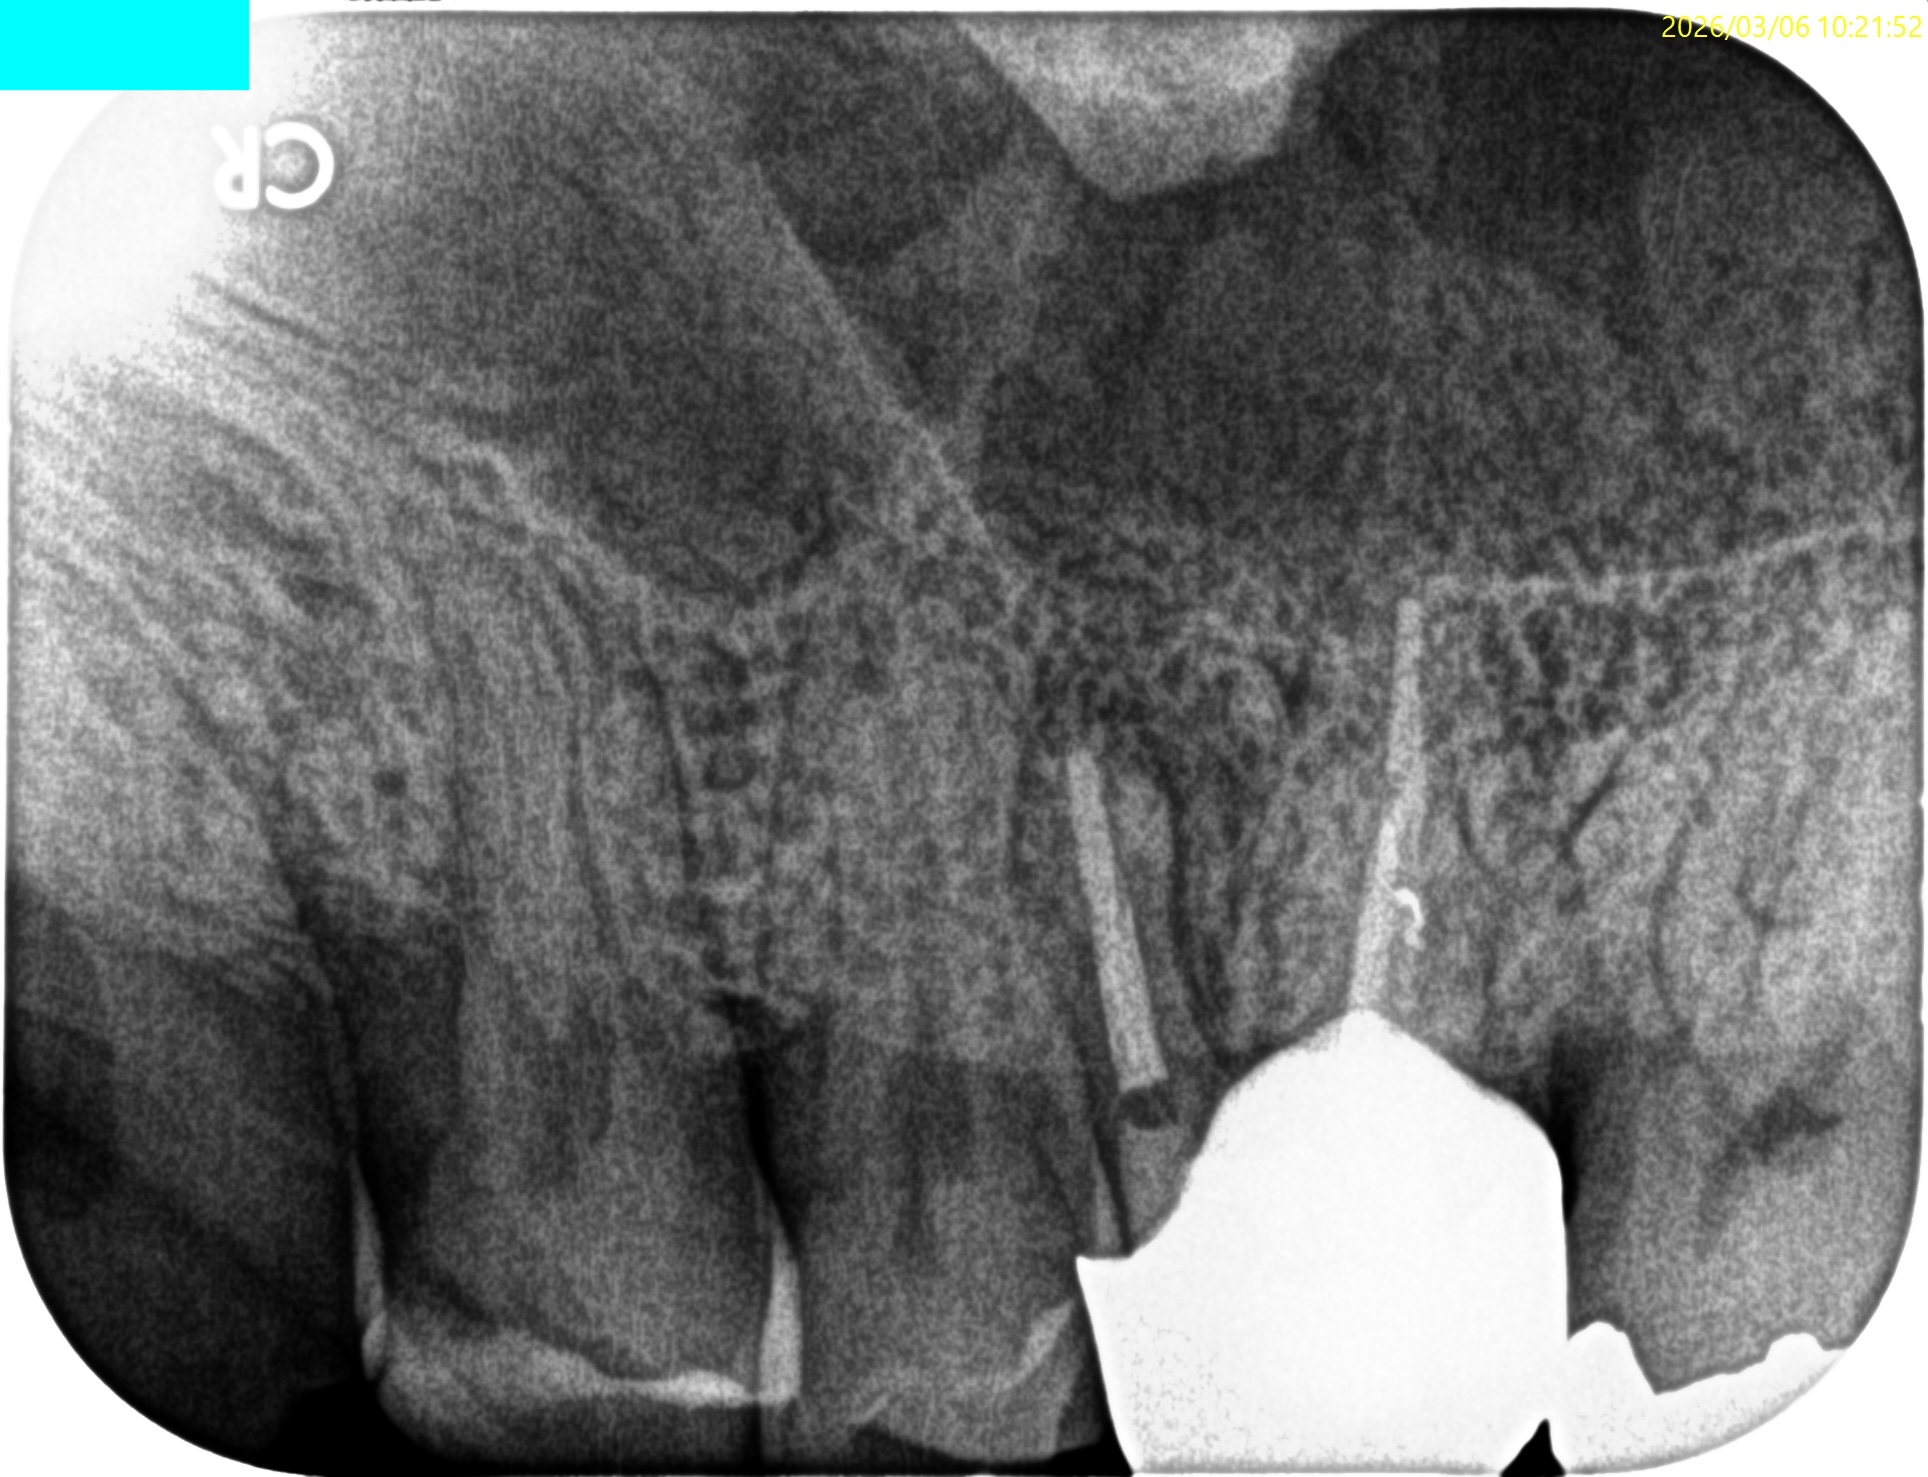

#14 MB Apicoectomy(2026.3.6)

MBの切断面が

このような形状になっていることから切断に問題がないことがわかる。

そしてこれをRetroprepすると、

このような状態になることが予想できる。

ということでRetroprepした。

PA, CBCTを撮影した。

逆根管充填材が頬側に寄っているような絵である。